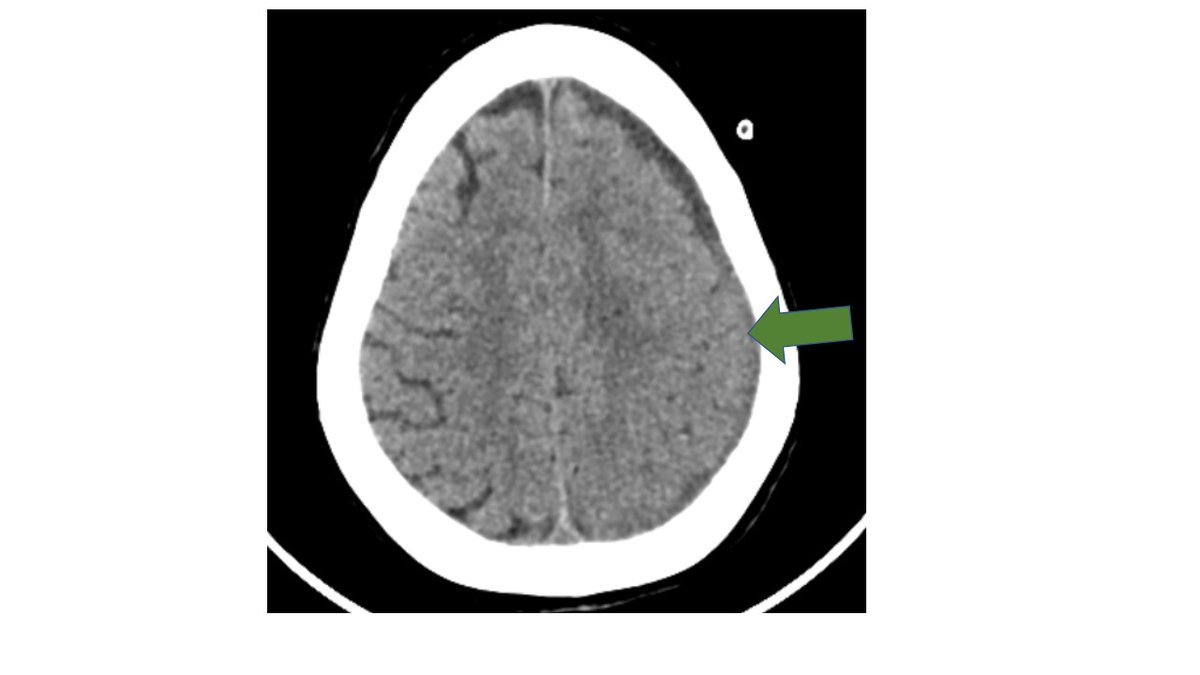

EEG- left hemispheric status epilepticus followed by PLEDS. CT is reported as subdural hygroma.

EEG shows left hemispheric rhythmic discharges s/o focal status epilepticus. A small subdural hygroma can't possibly cause this much trouble?

Clinical findings disproportionate to the imaging findings or underlying bacteremia, sepsis or immunosuppression should arouse the suspicion of a subdural empyema. Main d/ds are a subdural hygroma or hematoma. All of them can be hypodense to isodense to brain on NECT.